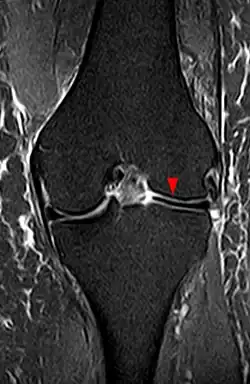

Röntgenuntersuchungen bringen wie auch Blutlaboruntersuchungen keine auffälligen Befunde. Selten können die seitlichen Gelenkspalten in normalen Röntgenuntersuchungen verbreitert erscheinen. Eine zuverlässige Darstellung von Scheibenmenisken findet sich nur im Rahmen einer kernspintomographischen Untersuchung. Hier können die Knorpelscheibe in ihrer Ausdehnung und Dicke sowie Risse im Gewebe und bisweilen die normale Fixierung des Meniskus an seiner Basis dargestellt werden.